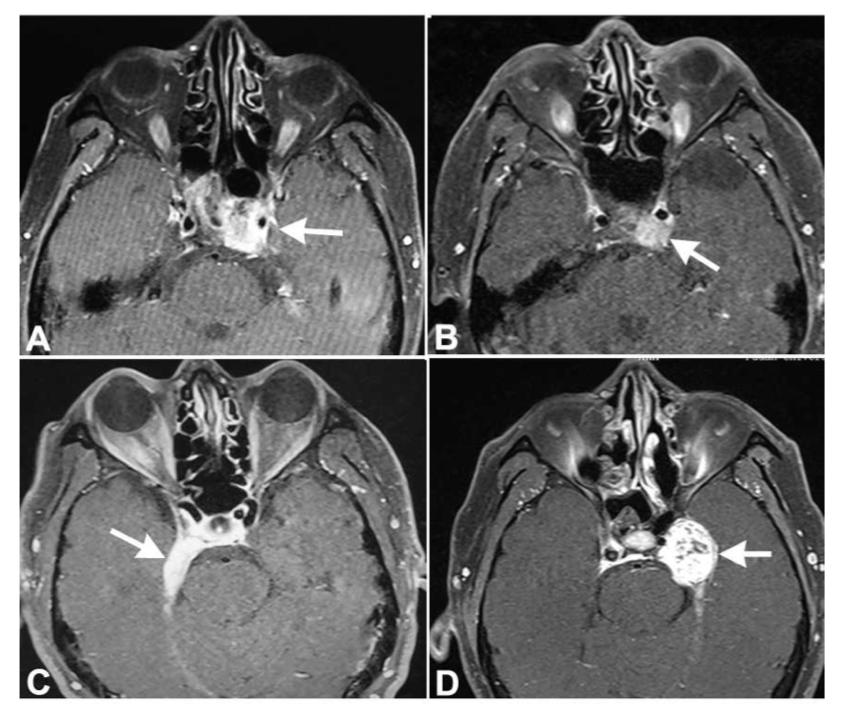

(3)肿瘤转移:很多肿瘤可以侵犯海绵窦:脑膜瘤、听神经瘤、脊索瘤、鼻咽癌、淋巴瘤、垂体腺瘤以及转移瘤。约20%鼻咽癌可以出现海绵窦症状。转移瘤中肺癌、乳腺癌和腺癌较常见。如果患者眼肌麻痹及海绵窦MRI异常对激素治疗反应不佳,需要进行全身仔细检查(图3)。

图3.海绵窦各种肿瘤病变MRI表现:(A):鼻咽癌患者左侧海绵窦转移(白箭)导致左侧外展麻痹;(B):甲状腺恶性肿瘤转移至左侧海绵窦(白箭);(C):左侧海绵窦脑膜瘤,导致患者慢性进行性右侧外展麻痹(白箭);(D):海绵窦三叉神经鞘瘤(白箭)。